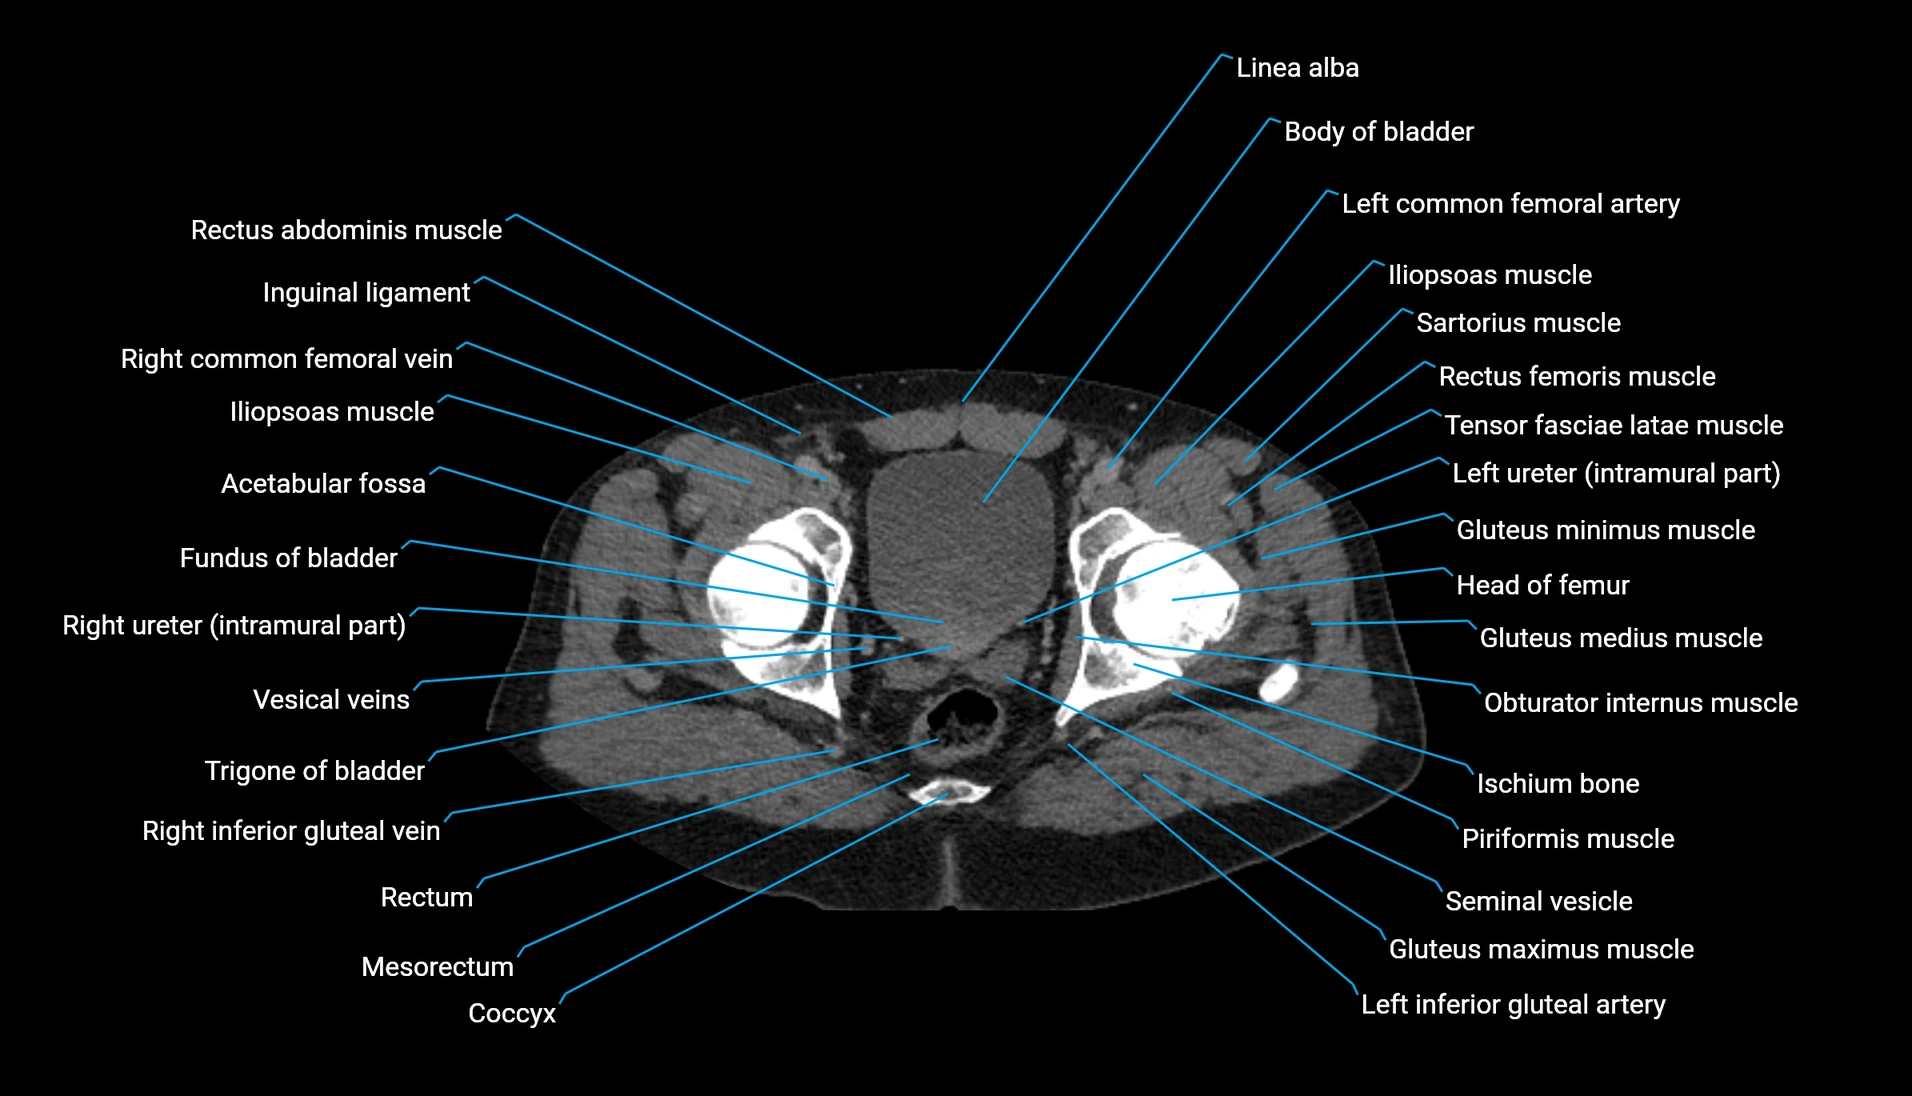

CT image